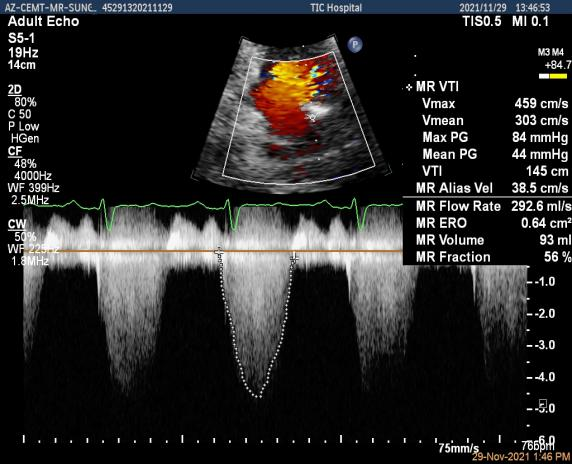

术前超声评估结果

术前超声诊断

3D-color MV view:大量反流,起源于1区